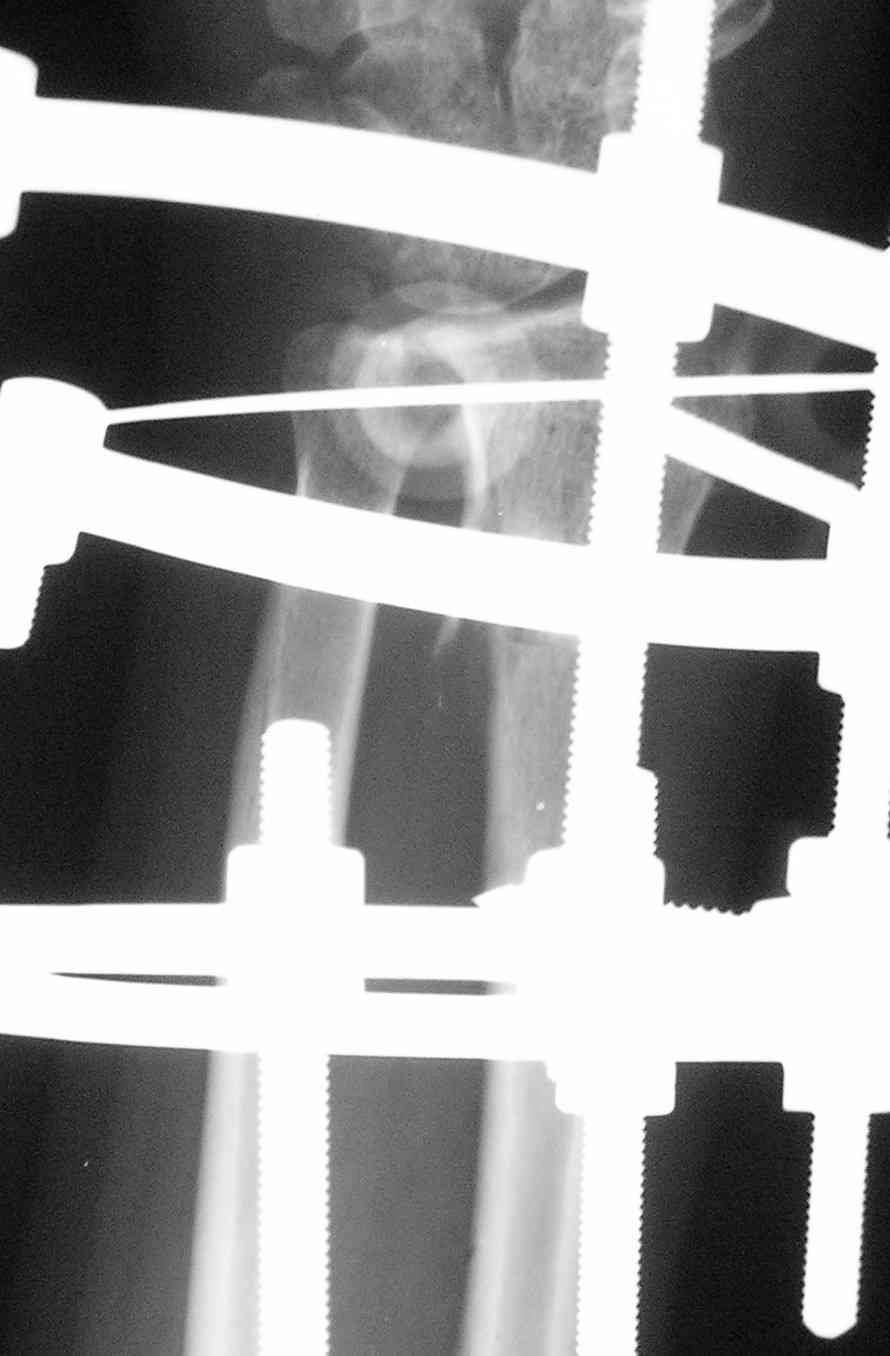

Саша, приветствую,

Конечно согласен с тобой, что не плохо бы было восстановить разгибание. Прежде чем планировать оклосуставные остеотомии, поговори со своими

коллегами, которые занимаются артроскопией, может они возьмутся *подбрить*

сустав и сделать капсульный релиз.

+ в постоп периоде в.суставное введение анастетика со стероидами и физиолечение улучшат амплитуду движений? По поводу дистракции л.з. сустава

в шарнирном аппарате- когда-то попалась статья по функциональной оценке лечения переломов дистального луча bridging and non bridging внешними фиксаторами и при восстановленной анатомии объем движений в группе c bridging ex fix. был значительно хуже - по -видимому, при растяжении капсулы теряется её эластичность, что и влияет на объем движений. У тебя больше опыт

работы с аппаратами, чем у меня, может быть я и не прав, но *за что купил, за то и продал*, поэтому сам стараюсь никогда не *перекрывать* сустав в

аппарате.

операцию А.М. Лаврукова упоминали на форуме, насколько я понял, она показана при псевдоартрозах ладьевидной кости с последующим формированием

артроза радио-ладьевидного сустава, в случае, который ты показал дегенеративные изменения очевидны и в радио-лунарном отделе сустава, следуя

логике, декомпрессия только одного отдела маловероятно улучшит функцию сустава в целом, мне так кажется. Отправлю тебе картинку с 6 летним результатом после проксимальной карпальной

резекции - для меня убедительно, может быть для тебя тоже будет интересна.